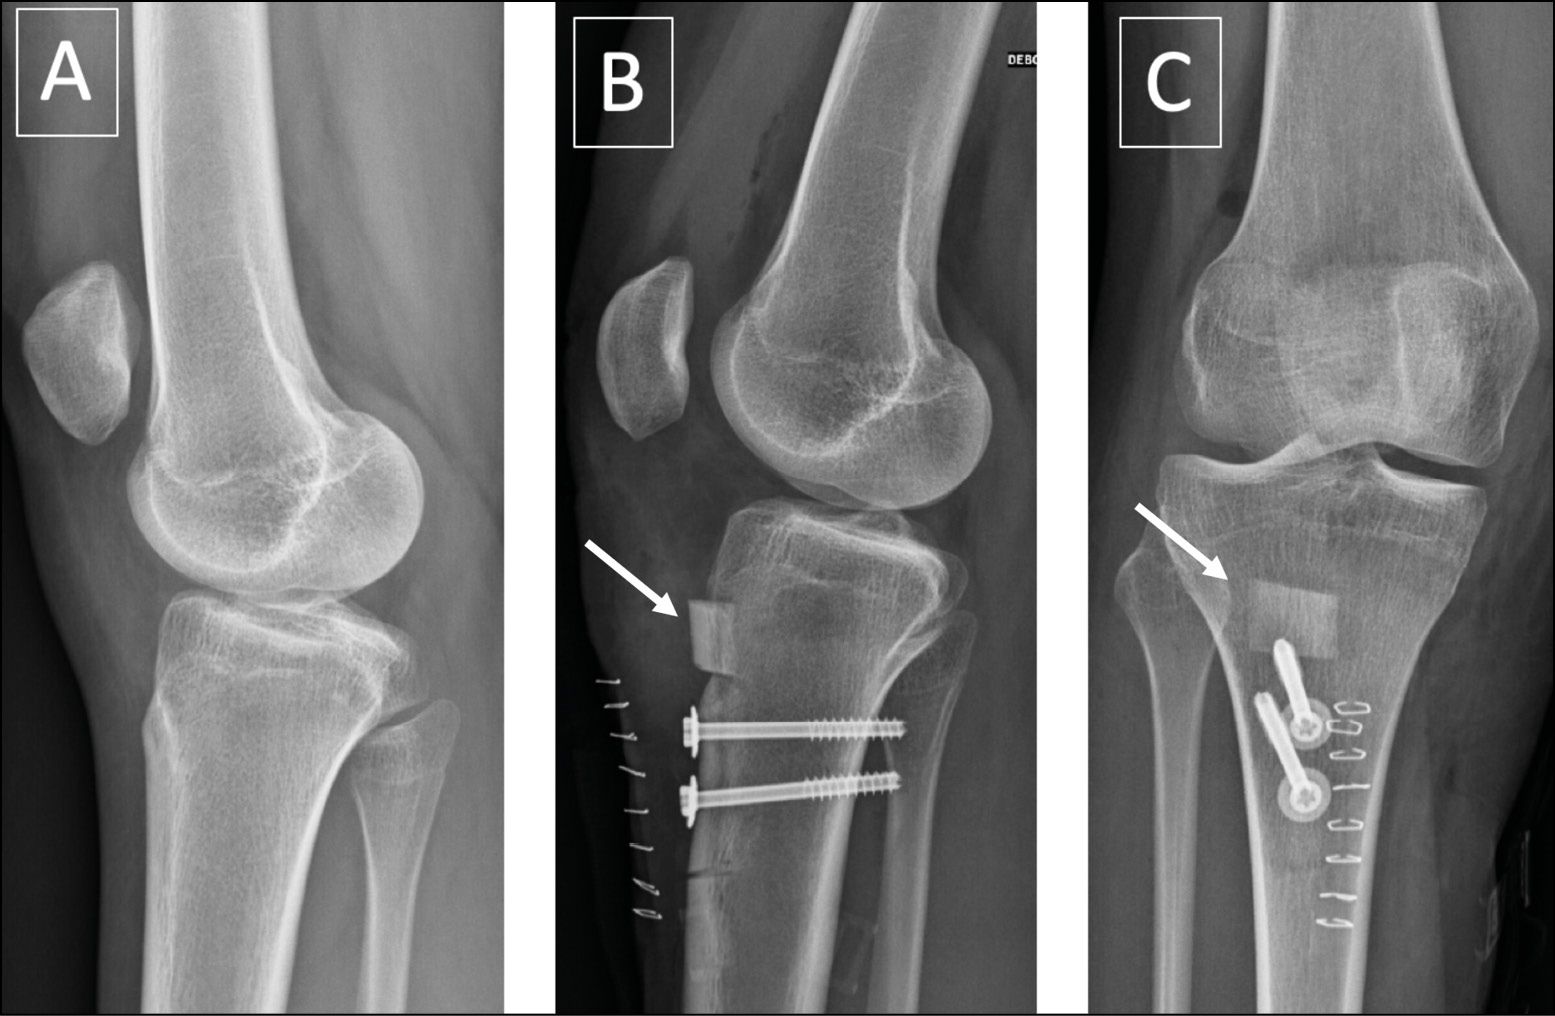

The skin incision should be wide enough to remove a wedge at least 6cm long. The distal insertion of the PT is located and dissected to allow through a Farabeuf retractor for protecting the tendon during the cut and possibly make a chamfer. The location of the ATT bony wedge and the two drill holes are marked with electro cautery to avoid an overly short wedge or holes too close together, which would weaken the bone. The two holes are drilled with a 4.5 mm drill before the cut, but only as far as the primary cortex, so that the wedge can be compressed during fixation. Just before making the cut with an oscillating saw, two additional holes may also be made using a size 2 drill at the distal end of the wedge to avoid fracturing the tibia. The medial part of the cut should be horizontal and the lateral part made at a 45° angle to avoid damaging the skin and tibialis anterior muscle with the blade (Fig. 4).

The flat cut in the medial cortex makes it possible to move the wedge without any bony obstruction, and the lateral oblique cut will pass through cancellous bone which will subsequently aid consolidation of the ATT.

The bone wedge is entirely freed from all adhesions so that it can be easily lowered, including section of the retinacula using Mayo scissors. A roughly 1cm bone fragment removed from the tibial crest can then be embedded just above the ATT bony wedge (Fig. 5).

It must be firmly embedded in the cancellous bone using a tamp to avoid impinging on the deep surface of the patellar tendon. Once the wedge has been lowered, it is temporarily held in place using a Steinmann pin inserted through the proximal hole and fixed in the posterior cortex. A 3.2 drill is then used to drill down into the posterior cortex of the distal hole, before inserting a size 4.5 screw, but without over-tightening it at first and the same procedure is repeated for the proximal hole. Take care to place the screws perfectly perpendicular to the tibial diaphysis and be sure that both screws protrude by 2mm the posterior cortex to limit the risk of secondary detachment of the wedge. The two screws are then successively and gradually tightened to compress the wedge sufficiently but without splitting or tilting it.

The key outcome of this procedure is the target postoperative Caton-Deschamps score or sagittal engagement score, which should usually be around 1 for the Caton-Deschamps score and positive for the sagittal engagement score. The ability to achieve these target scores depends crucially on the preoperative planning: full-scale x-rays or MRI, depending on the chosen score. Fluoroscopy may also be used to check the height during the procedure.